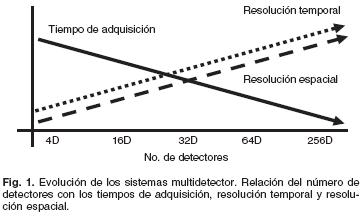

La TC incursionó en la evaluación cardíaca en 1984 con la introducción de la TC por emisión de haz de electrones (TCEE). La TCEE cuenta con numerosas limitaciones, entre ellas una baja resolución espacial (1.5–3 mm), tiempos de adquisición prolongados (40–50 latidos cardíacos por estudio), imágenes con bajo índice señalruido y baja disponibilidad. Más recientemente, con el desarrollo de la TCMD la imagen topográfica cardiovascular es una realidad.5 Los avances tecnológicos de la TCMD se han enfocado en aumentar el número de detectores dispuestos en el eje z y a disminuir su tamaño, a incrementar la velocidad de rotación del tubo de rayos–X, y a mejorar los protocolos de reconstrucción (Fig 1). Hoy día es posible obtener imágenes tridimensionales del corazón y del cuerpo entero en segundos.10 La TCMD del corazón cuenta con las siguientes ventajas: es un método no invasivo, rápido (tiempo en sala de 10 minutos y de adquisición de 15 segundos), con capacidad multiplanar, de menor costo que la angiografía, y que genera imágenes cardíacas y extracardíacas sin la interferencia o sobreposición de estructuras adyacentes.

En resumen, la mayor velocidad de giro del tubo de rayos–X, los nuevos algoritmos de reconstrucción y acoplamiento ECG, la disminución del tamaño de los detectores y el incremento en su número, permiten una mejoría sustancial de la resolución temporal y espacial, además de haber reducido los tiempos de adquisición respectivamente (Fig. 3). Finalmente, a la par de estos avances, también se han desarrollado tubos de rayos X de mayor corriente, lo cual incrementa el índice señal/ruido y por ende la calidad de la imagen.